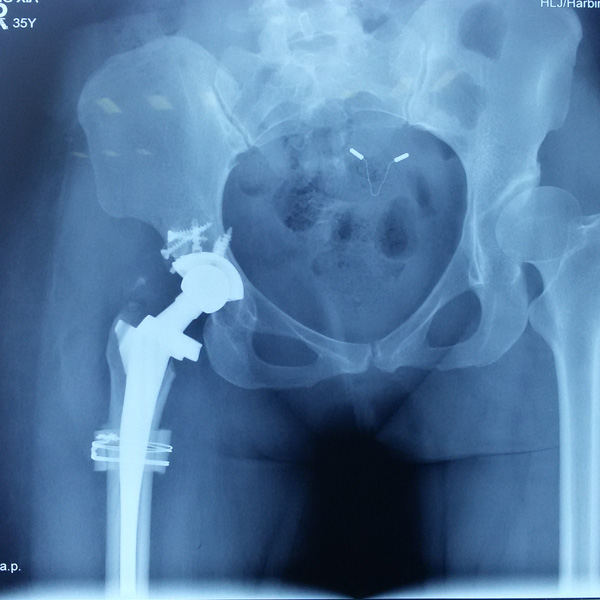

先天性髖關(guān)節(jié)脫位

患者王某某,女,41歲,從會走路以來就發(fā)現(xiàn)一條腿長,一條腿短,也就是人們俗稱的“跛子”,之前雖然兩條腿長短不一,但起碼還可以走路,維......